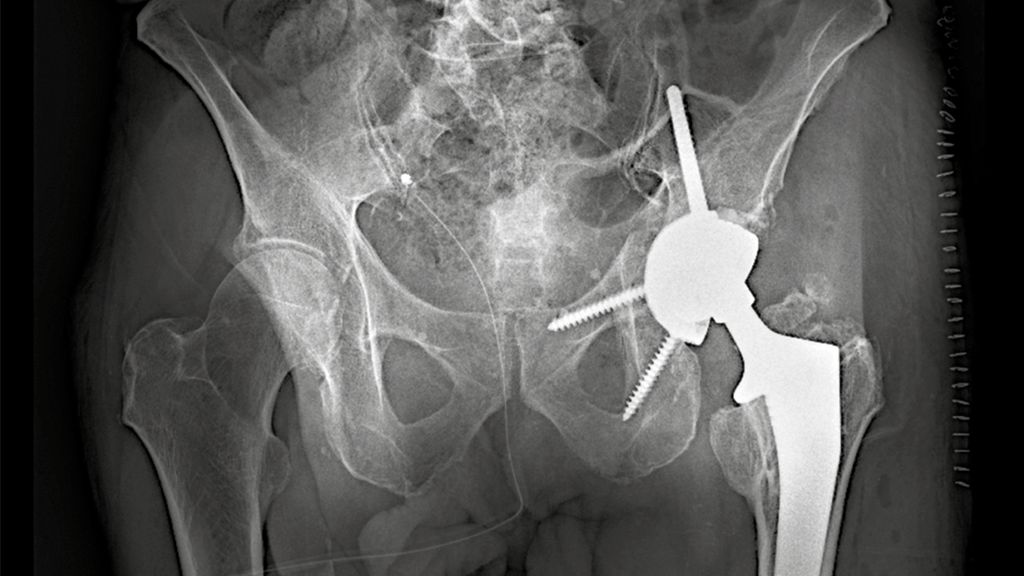

Implantation der PRS-Rekonstruktionspfanne

Die PRS-Pfanne zeichnet sich durch ihre massive Bauweise, multiple Schraubenoptionen und die Möglichkeit einer zentralen Ileumschraube aus. Nach Einbringen der Pfanne wird diese korrekt ausgerichtet (Inklination ca. 40–45°, Anteversion ca. 15–20°). Der entscheidende Schritt ist die Platzierung der zentralen Ileumschraube. Dafür wird unter Bildwandlerkontrolle ein Bohrdraht in den supraazetabulären Korridor gesetzt (Abb. 3a u. 3b) und mit dem 6-mm-Bohrer überbohrt. Anschließend wird die Schraube durch das entsprechende Positionsloch der Pfanne in den supraazetabulären Anteil des Iliums eingebracht. Dabei ist auf eine ausreichende Schraubenlänge zu achten, um eine stabile Verankerung zu erzielen. Die zentrale Schraube übernimmt eine lasttragende Funktion und wirkt wie eine intrapelvine Abstützung. Zusätzlich wird die Pfanne mit Schrauben im Sitzbein und/oder dem Schambeinast fixiert (Abb. 4). Die PRS-Pfanne erlaubt hierbei eine flexible Schraubenplatzierung, was insbesondere bei komplexen Frakturmorphologien von Vorteil ist.